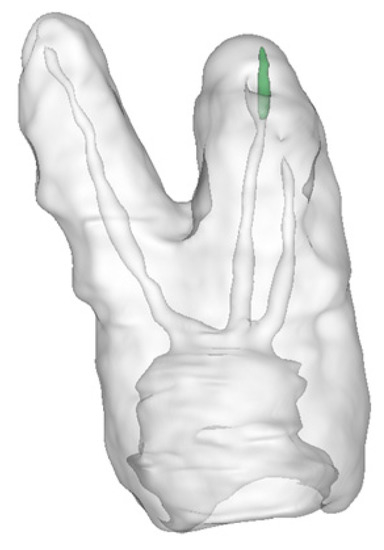

Various types of software and hardware tools are required to develop and visualize holographic 3D models. In terms of hardware, the system is designed to run on Microsoft HoloLens 2. The structural models of teeth and root canals are reconstructed by a developed Python application and the models are exported into Unreal Engine (Epic Games, Potomac, MD, USA). To create the holographic 3D models of patients’ teeth, which are presented in Figure 5, DICOM RAW data from CT scans were used. By applying semi-automated algorithms, the CT scan is segmented. Every elementary volume component (i.e., voxels or Hounsfield units) of the CT scan is labeled manually and then processed. Here, the fill-between-slices algorithm was used. The application, which enables the creation of 3D holograms, was written in Python, see Figure 6. In the first step, a CT scan (DICOM data) was loaded. Next, each layer was reviewed to obtain the required range of minimal and maximal values for the entire CT scan. The values obtained are applied to select the appropriate range to obtain the best quality model. For example, the range of 0–50,000, where 0 denotes a black color and 50,000 white colors. The created range selection enables us to decide which pixels should be skipped in the generated model. It can be compared to printing black pictures on white paper. The printer is only placing black ink in black spots on white paper and skips everything where it should print in white color. Creating 3D models is the same situation. We decide which color values from the DICOM pictures should be used for creating the model and which are skipped as empty spaces.

In the first case, the patient was referred to endodontic treatment, while in tooth 17, carious pulp exposure was detected. It was a deep subgingival carious lesion. Thus, the patient considered extraction and implant placement, and as a consequence, the patient was referred for microCBCT. Upon analyzing the scans together with the patient, a decision was made to perform endodontic treatment. On the CT performed, four roots with canals of significant curvature are visible. All four canals were chemomechanically prepared and filled. Finally, the endodontic treatment was successful. The procedure was performed without any complications thanks to the high accuracy of recognition of the course of all four tooth canals. The 3D of tooth 17 with carious pulp exposure was shown in Figure 8.

Figure 5. The 3D holograms of the tooth, with visible root canals.

Figure 8. The 3D of tooth 17 with carious pulp exposure.